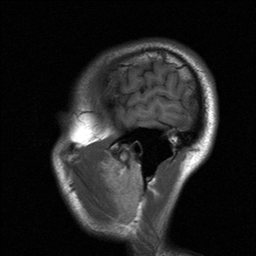

One MRI Sunday Morning…

I had an MRI done this Sunday Morning @ 9am. I asked for a copy of the images. Check out this animation that I made with some of the pictures:

Cool, innit? One thing – why am I being reminded of a certain cranially challenged cartoon character?